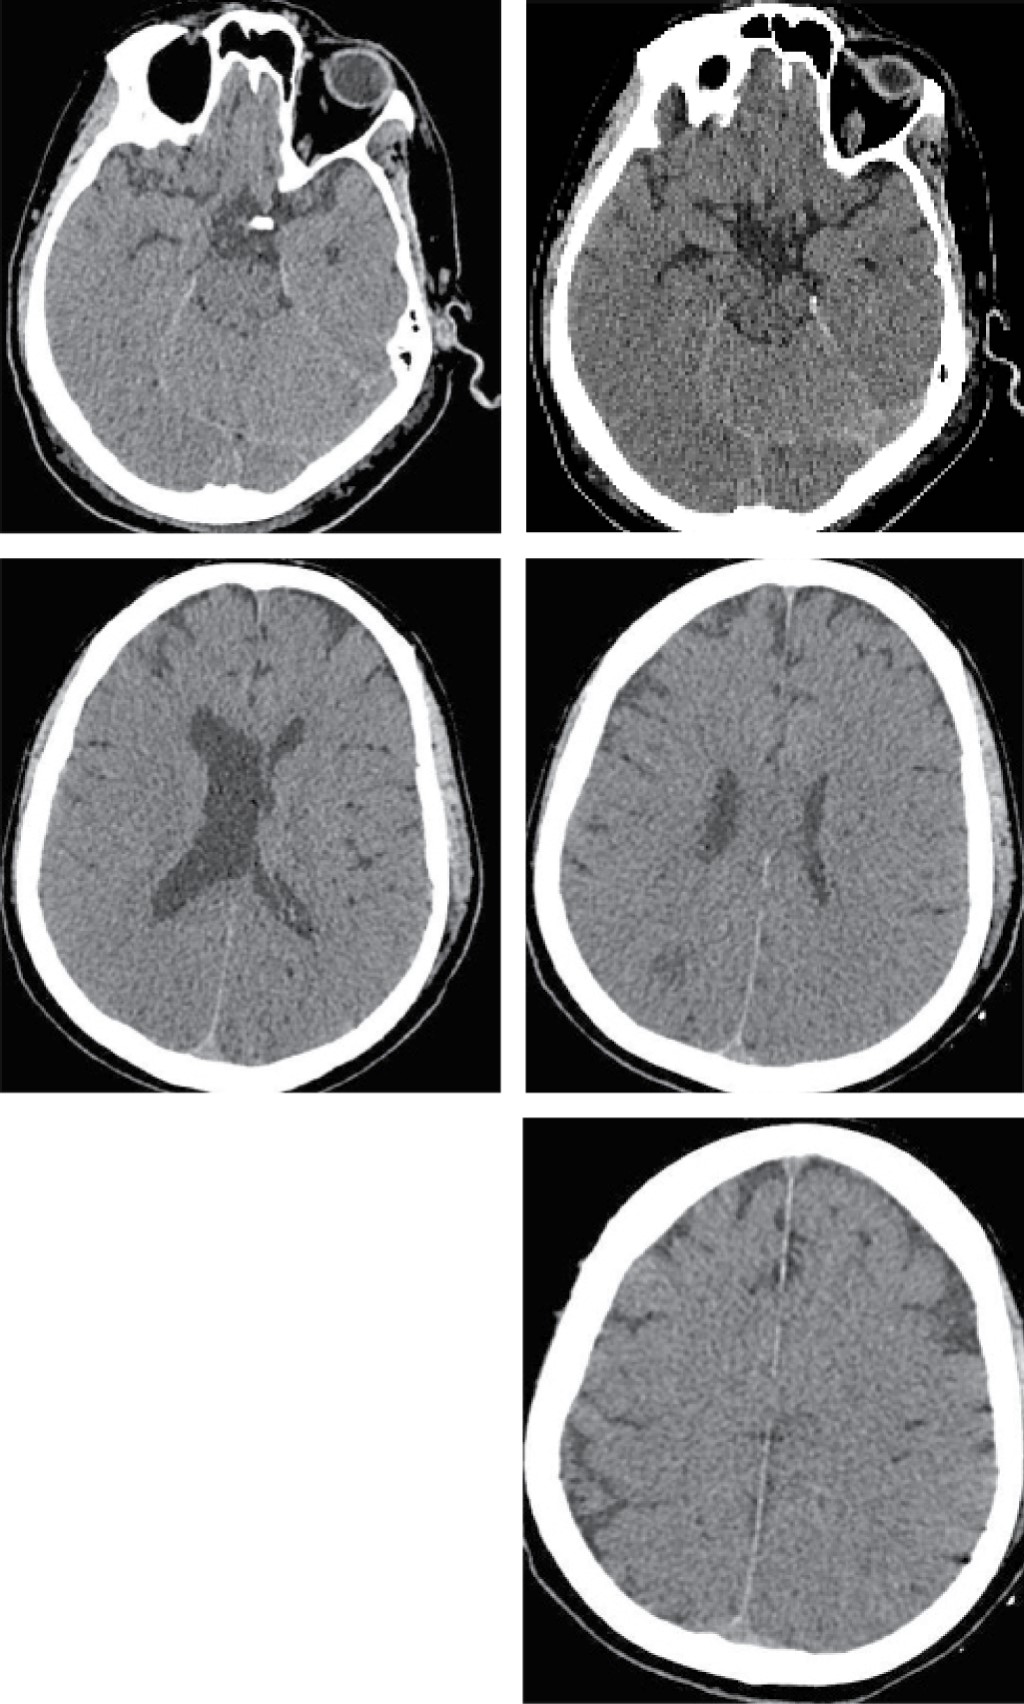

Subarachnoid hemorrhage in a patient with severe COVID-19 pneumonia, secondary to disseminated intravascular coagulation

This is a case report of a 63-year-old patient with SARS-CoV-2. Secondary to COVID-19 showing signs of severe pneumonia he is admitted to the intensive care service, requires advanced airway support and anticoagulation treatment at therapeutic doses. Derived from right hand thrombosis a tomographic study was carried out, reporting the diagnosis of Fisher 3 subarachnoid hemorrhage, the anticoagulation was suspended after 5 days, melena-type evacuations and expenditure by nasogastric tube in coffee grounds are manifested, with data of 95,000/μL thrombocytopenia, 198 mg/dL fibrinogen, INR 1.30, TTP 20.4 s, TP 12.7 s, meeting criteria of disseminated intravascular coagulation. The presentation of this case seems interesting because of the association that COVID-19 infection has to the alteration of such coagulation cascade, showing secondary bleeding.

Figure 2